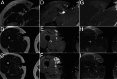

Multifocal desmoid-type fibromatosis (DTF) is very rare and usually regional. We report three cases that initially appeared to be multifocal, but subsequent detailed imaging revealed unsuspected tracking along nerves in two cases. This neural spread is reminiscent of neuromuscular choristoma (NMC), a rare developmental lesion in which mature skeletal muscle cells, or rarely smooth muscle cells, infiltrate and enlarge peripheral nerves. NMC is frequently associated with DTF. These two cases suggest that DTF spread along nerves and appeared as distinct multifocal lesions while actually being contiguous. The third case was felt to represent true multifocal tumor development, possibly due to tumor seeding at the time of chest surgery. The relationship of DTF to NMC is discussed.